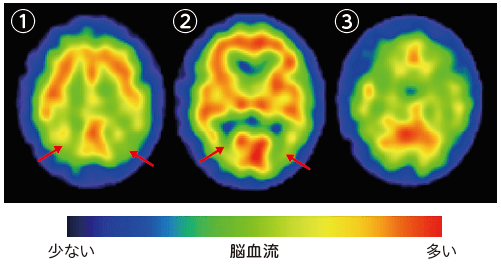

spectの画像

![spect 撮って診る認知症genki55.net|SPECT検査[認知症の進行状況がわかる]](http://genki55.net/img/spect09.gif)